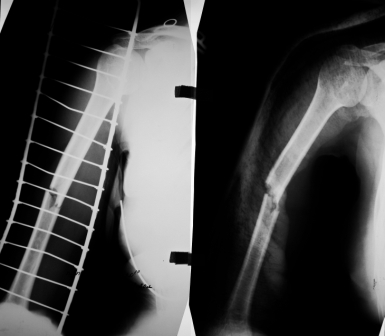

Уважаемые коллеги, представляю вашему вниманию контрольные рентгенограммы.

Насчет косметичности именно внешней фиксации в сравнении с малоинвазивной внутренней - вот примерчик. Первое фото после снятия аппарата перед штифтованием, а воторая картинка через год после штифтования. Поглядите, от чего осталось больше следов.